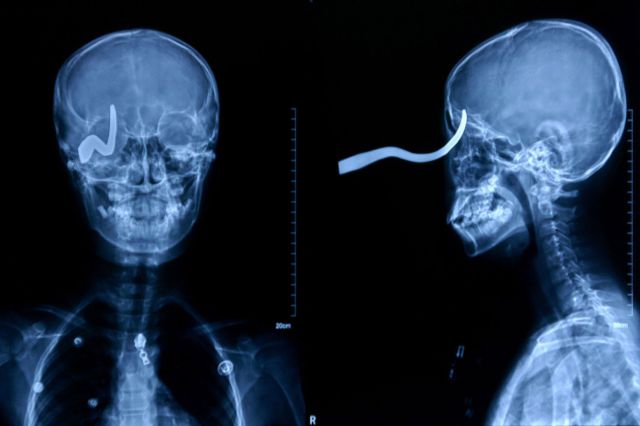

Eleven-year-old Chinese schoolboy Liu Cheong had a brush with death when his friend shot him in the head with a 16-inch arrow, according to numerous international media reports. The arrow entered his skull through the eye socket and lodged in the back of his head. Somehow, the boy was spared a fatal brain injury.